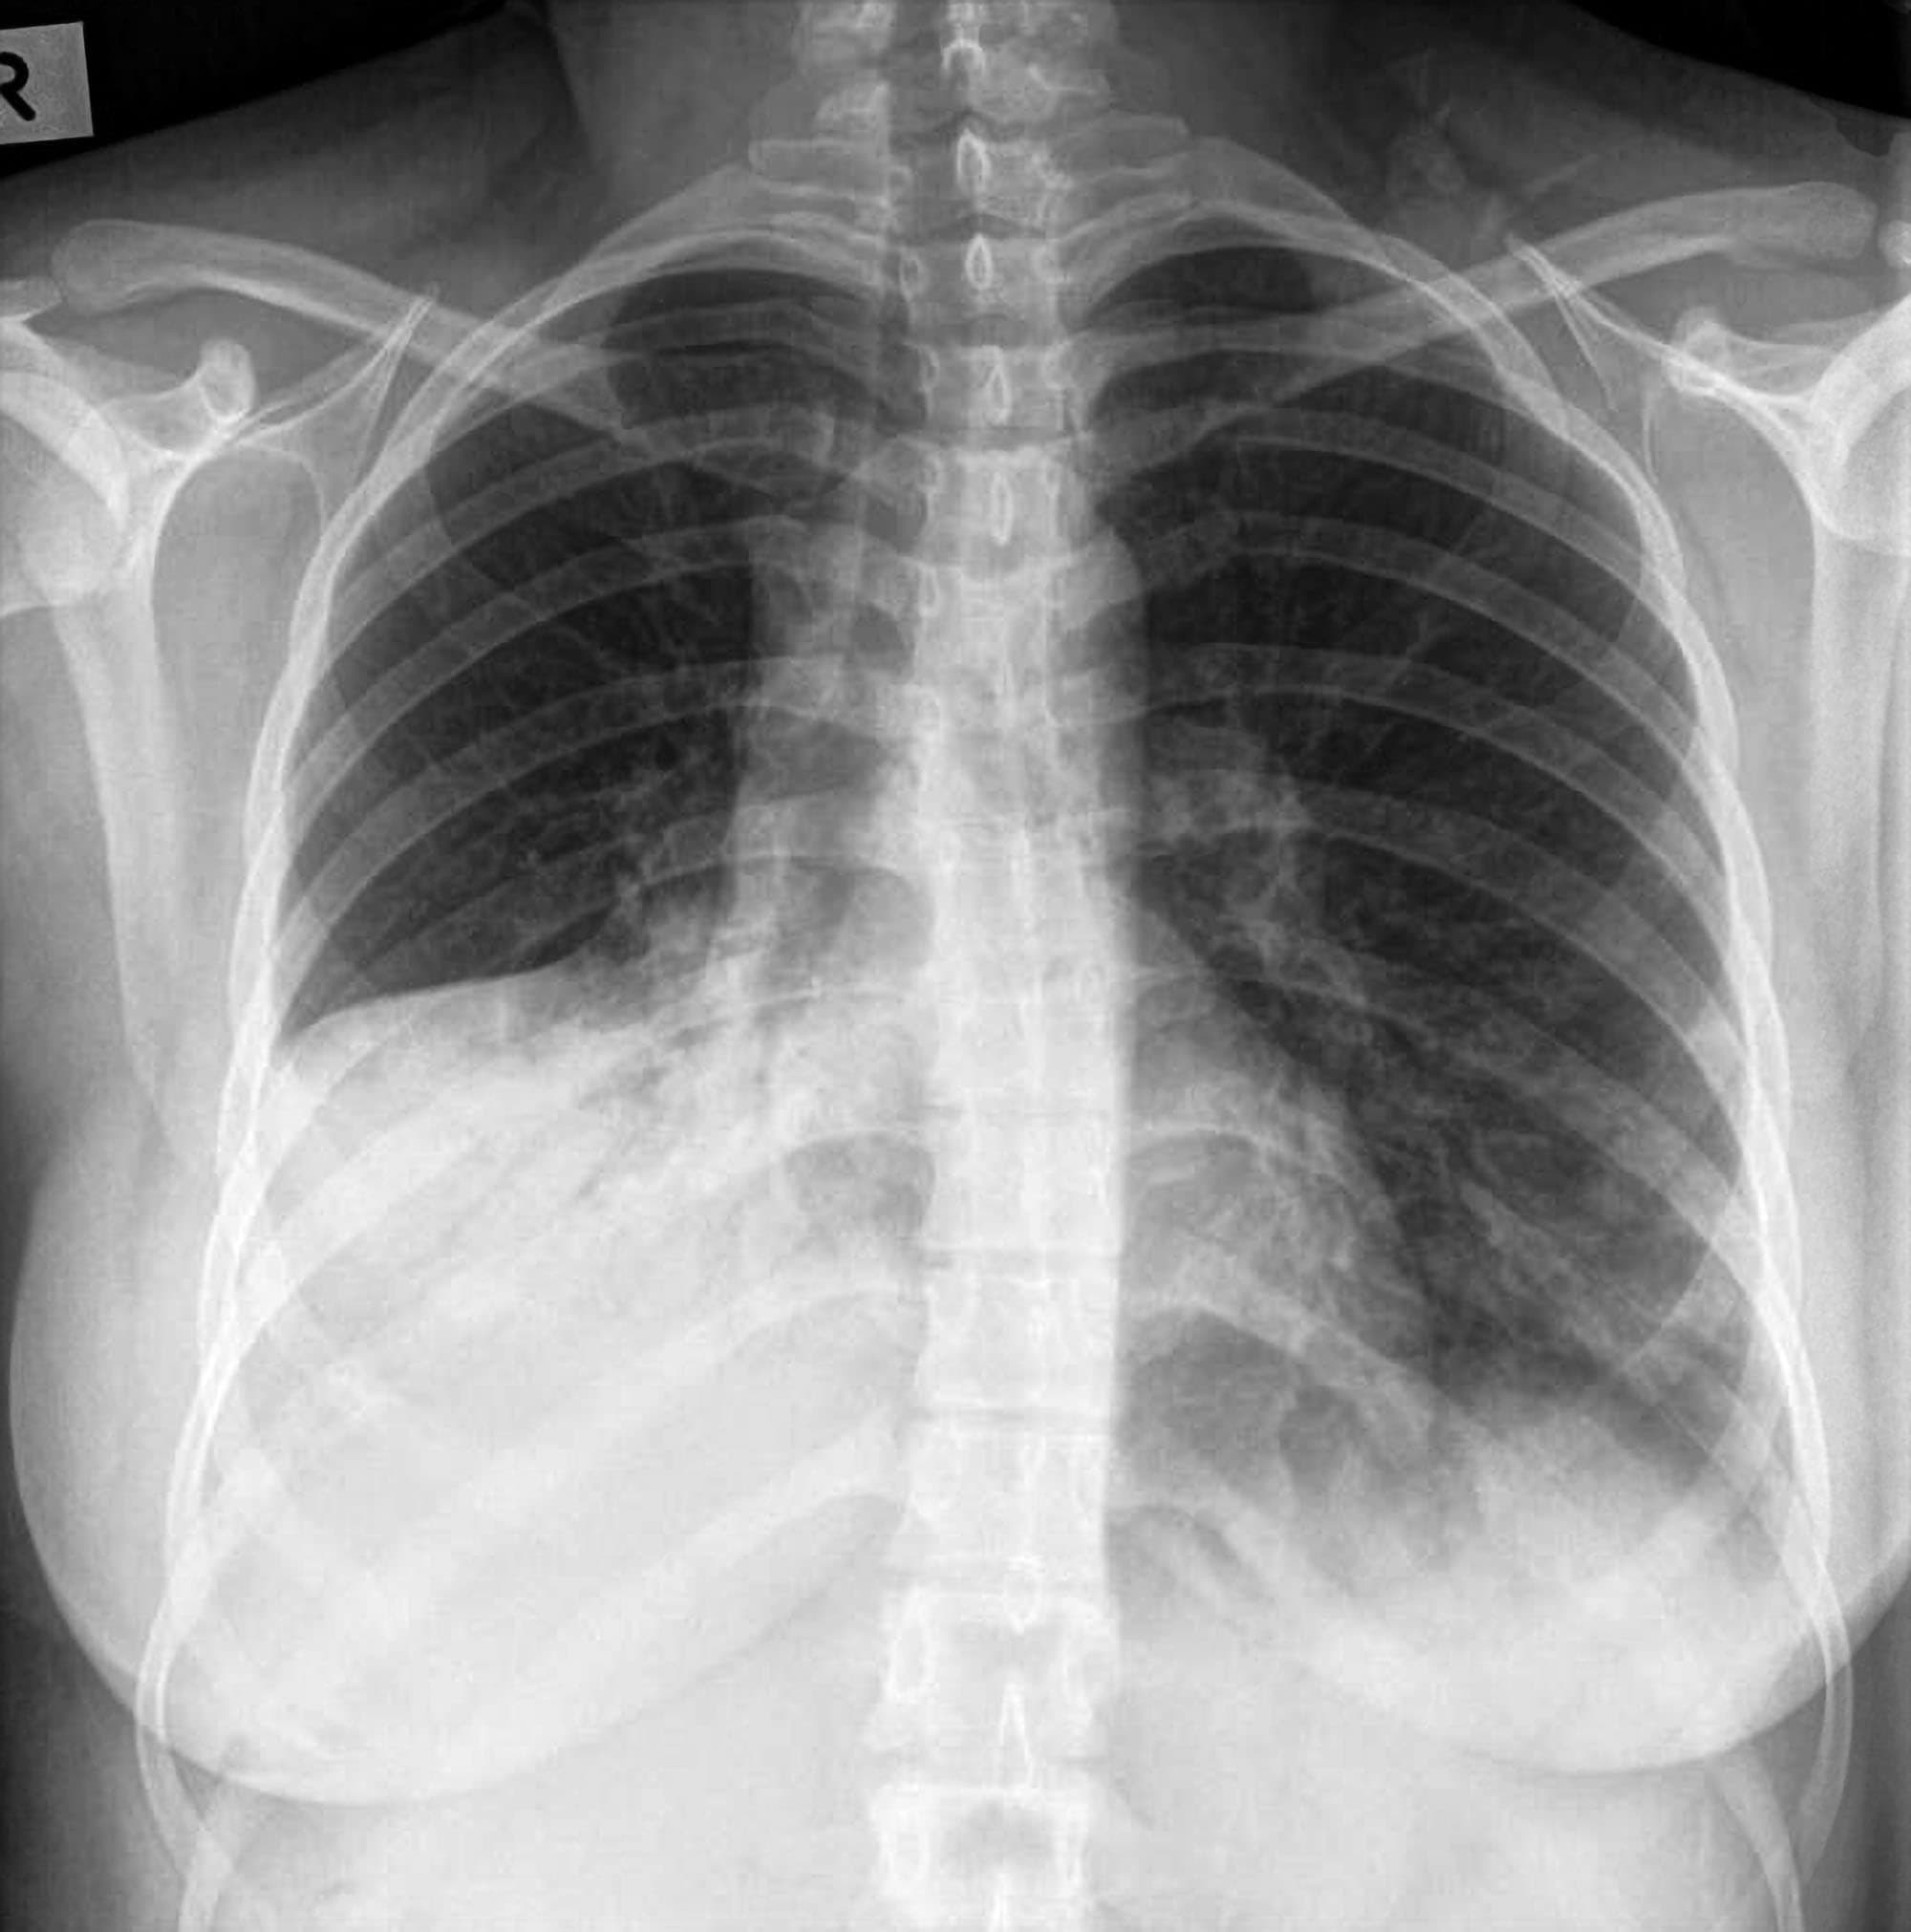

Chest X-Ray | Cardiovascular Medical Group of Southern California

Chest xray normal vs abnormal – wholelopez